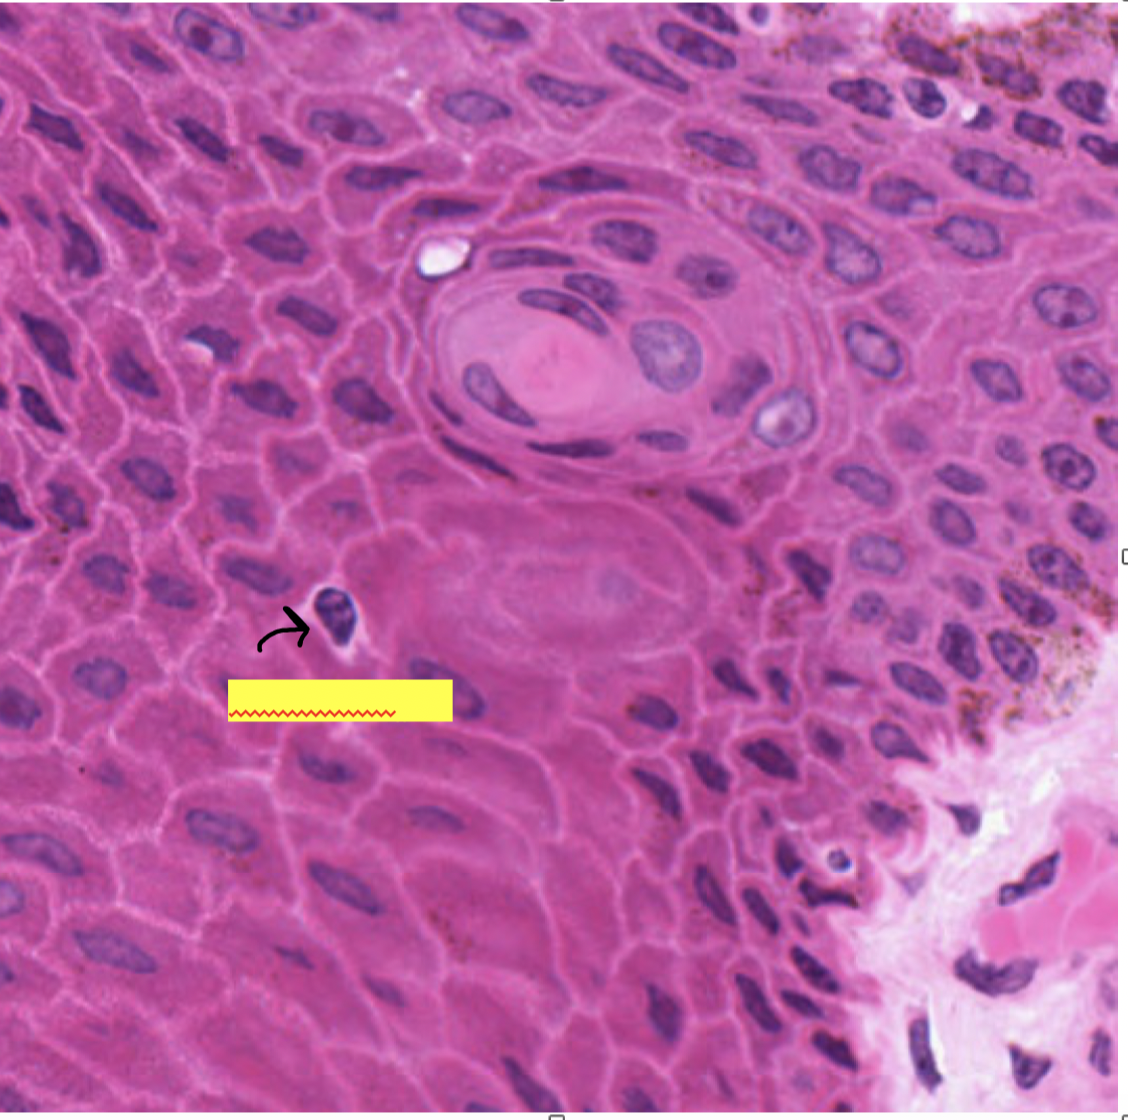

which layer is filled with dead cells and sloughs off

which layer has desmosomes linking it together

which layer contains melainin granules

what is a clear homogenous layer just superficial to the stratum granulosum